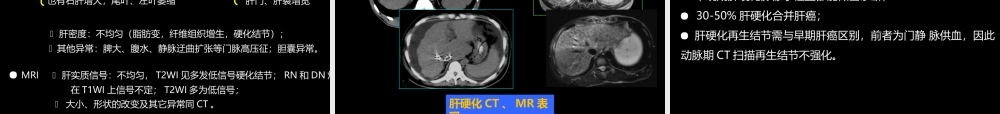

肝胆胰影像学诊断中国石油中心医院影像学教研室杨景震(X线、超声、CT、MRI)注:使用幻灯放映模式浏览2014-10修改版肝脏1、X线平片:很少应用;肝脏血管造影:很少用于诊断,更多的用于介入治疗2、超声检查:常用的检查方法3、CT检查:主要的检查手段之一⑴平扫⑵增强:多期增强;动态增强;CT灌注(一)检查技术4、MR检查:一般认为是在超声检查或CT检查之后的检查。用于疾病的鉴别或早期癌灶的检查与诊断(1)平扫:多种成像序列,用于获得更多的信息(2)增强:多期增强,使用Gd-DTPA.(3)使用特殊对比剂:2类:超顺磁性氧化铁,被肝内网状内皮系统的Küpffer细胞吞噬,据此可推断病变内是否有此种细胞。另一类为肝细胞特异性对比剂(如钆塞酸二钠),被肝细胞摄取、转运,可用于肝细胞癌检出。(一)检查技术(二)正常影像表现1、肝脏位置与形态:2、肝脏的大小:超声测量:右叶前后径8-10cm;最大斜径为10-14cm;左叶厚度不超过6cm;长度不超过9cm。3、肝叶、肝段划分:4、肝实质:5、肝血管:1、肝脏位置与形态:2、肝脏的大小:3、肝叶、肝段划分:肝脏分右叶、左叶和尾叶。为适合外科学需要,影像检查根据肝内血管分布特点把肝脏划分为若干肝段。通常以肝右、肝中、肝左静脉作为纵向划分标志,以门静脉左右支主干作为横向划分标志,如此将肝脏划分为八个肝段。4、肝实质:5、肝血管:Couinaud根据肝内门静脉干和肝静脉的分布范围,将肝脏分为八段,门静脉分支分布于肝段内,而肝静脉位于肝段间。具体如下:以肝中静脉所在纵行平面将肝脏分为左右半肝,以肝左静脉为界将左半肝纵行分为左内与左外叶,而左外叶以门静脉左支为界水平分为上下两段,以肝右静脉纵向、门静脉右支横向将肝右叶分为上下前后四段,而肝尾叶为单独的一段,即:S1为尾状叶,S2为左外叶上段,S3为左外叶下段,S4为左内叶,S5为右前叶下段,S6为右后叶下段,S7为右后叶上段,S8为右前叶上段。1、肝脏位置与形态:2、肝脏的大小:3、肝叶、肝段划分:4、肝实质:超声肝实质均匀一致中等回声;CT为高于脾脏密度(CT值:55-75HU),其中血管为圆形或管状低密度。多期增强肝实质动脉期强化不明显,门静脉期强化开始明显,于平衡期强化达到高峰;MRI检查,肝实质信号均匀,其信号在T1WI高于脾脏,T2WI低于脾脏。多期增强特点同CT。1、肝脏位置与形态:2、肝脏的大小:3、肝叶、肝段划分:4、肝实质:5、肝血管:肝动脉、门静脉由肝门入肝;肝静脉于第二肝门汇入下腔静脉。(1)DSA:不同...